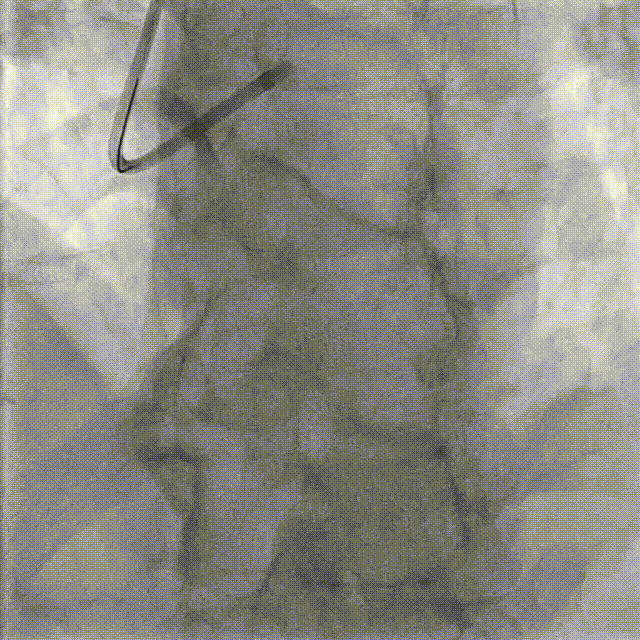

PCI-LAD TR, 7F EBU3.5

ROTA with 2.0mm burr

Angiography & Angioplasty NC 2.5*12mm